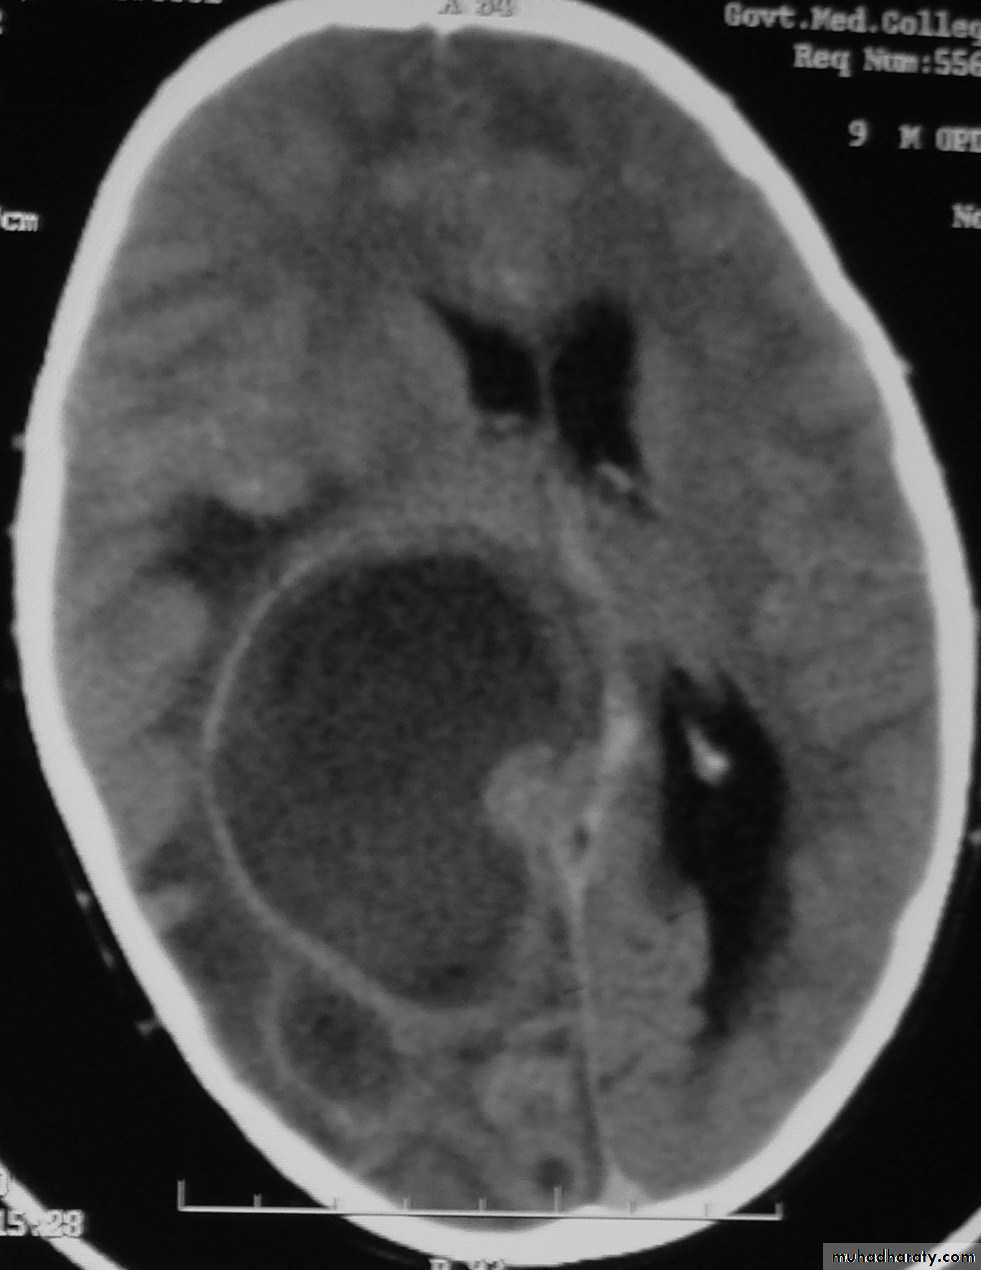

Brain Abscess CT without contrast

Brain Abscess CT with contrast